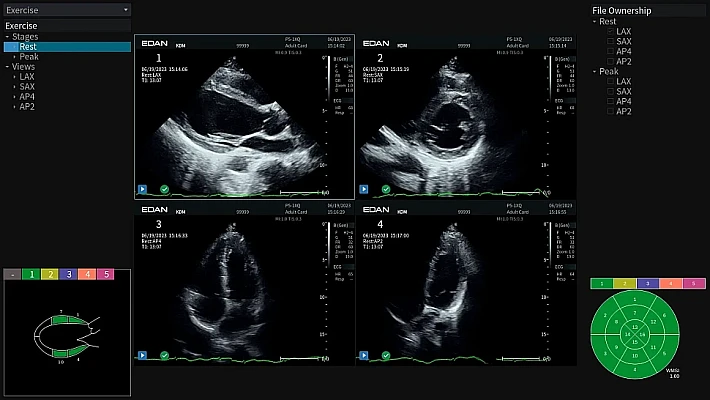

Медицинское оборудование и сервисное обслуживание